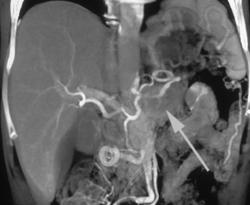

Cancer of the Pancreas With Carcinomatosis